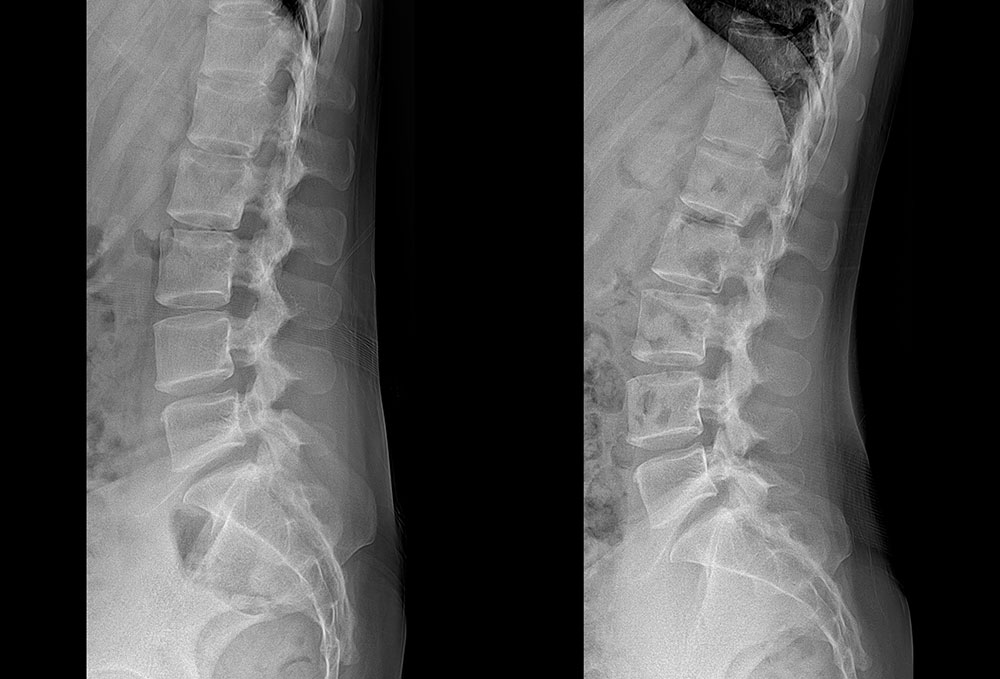

ÃÊÀ½ÆÄÁø´Ü ÇÁ·Ñ·ÎÄ¡·á ü¿ÜÃæ°ÝÆÄ µµ¼öÄ¡·á ¿ÀÇǽºÁúȯ °üÀý¿°Ä¡·á Ä¡·á Àü/ÈÄ »çÁø Ä¡·á Àü/ÈÄ »çÁø °ÅºÏ¸ñ µµ¼öÄ¡·á 10ȸ ÈÄ °ÅºÏ¸ñ µµ¼öÄ¡·á 8ȸ ÈÄ Ç㸮ÅëÁõ¡¤´Ù¸®Àú¸² µµ¼öÄ¡·á 10ȸ ÈÄ °ñ¹Ý Ʋ¾îÁü µµ¼öÄ¡·á 12ȸ ÈÄ Ã´Ãß Ãø¸¸Áõ ¹× Ç㸮ÅëÁõ µµ¼öÄ¡·á 15ȸ ÈÄ